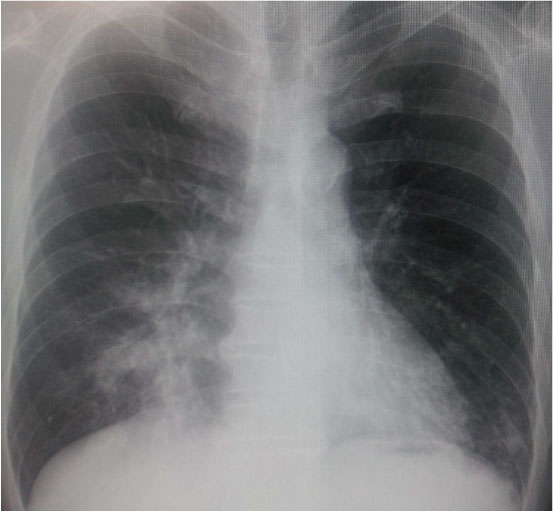

・外泊後、38℃以上の発熱。PaO2低下あり、酸素投与。

・胸部Xp

・喀痰塗抹検査:ガフキー9号

・喀痰PCR検査:結核菌